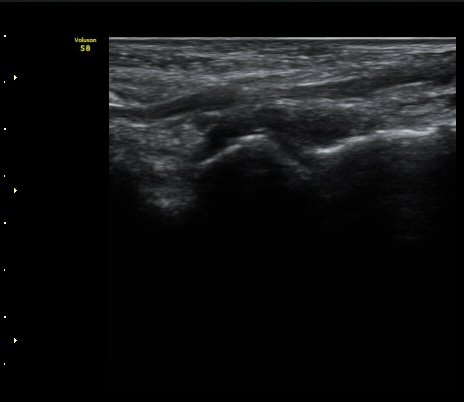

Á¾°ñÀÔ¹æ°ñÀδëÀÇ Á¾´Ü¸é°Ë»ç¿¡¼­ ÀδëÀÇ Á¾°ñ ºÎÂøºÎ ÆÄ¿­ÀÌ °üÂûµÊ(»çÁø 1, 2, 3).